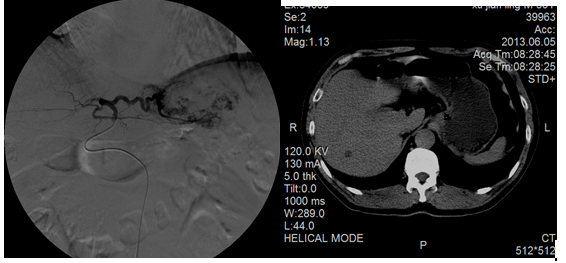

微创经皮肝动脉栓塞治疗肝海绵状血管瘤

肝海绵状血管瘤是人体常见良性肿瘤,常不需治疗,但对于1、肿瘤直径>5厘米,2、肿瘤位于肝包膜下,3、肿瘤压迫肝脏组织引起肝功能异常,4、患者心理负担重者需治疗,传统手术治疗创伤大,风险大,费用高,介入治疗可轻松根治!

患者、男、57岁,2011年6月CT及MR诊断肝海绵状血管瘤,在我院行肝动脉栓塞后,2013年6月复查